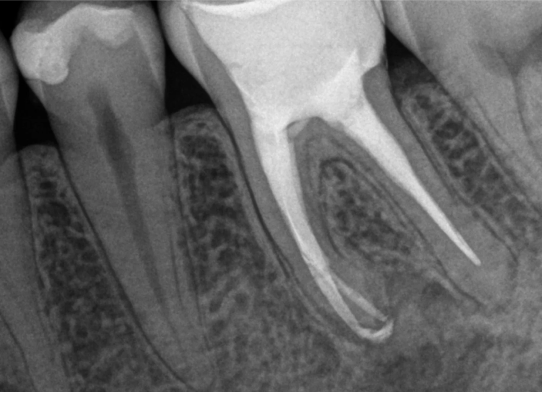

Po zakończonym leczeniu kanałowym, wykonujemy kontrolne zdjęcie RTG. Pozwala ono na natychmiastową ocenę jakości wypełnienia kanałów korzeniowych i potwierdzenie skuteczności przeprowadzonego zabiegu. Dla nas leczenie kanałowe Opole to synonim precyzji i pewności.

Na podstawie zdjęcia rentgenowskiego określa się kształt i długość kanału bądź za pomocą specjalnego urządzenia mierzy się jego długość. Potem lekarz otwiera wejścia do kanału, chroniąc ząb koferdamem, czyli specjalną gumą, zapewniającą sterylność oraz chroniącą przed środkami chemicznymi służącymi do oczyszcza-nia kanału. Używa się do tego zarówno specjalistycznego sprzętu, jak i nowo-czesnych mikroskopów, pozwalających na uzyskanie dokładnego obrazu leczone-go zęba. Ostatnią czynnością jest wypełnienie materiałem światłoutwardzal-nym i zabezpieczenie zęba przed dostaniem się i rozwojem bakterii mogących wywołać wtórny stan zapalny.

Przed rozpoczęciem leczenia kanałowego kluczowa jest dokładna diagnostyka. Zazwyczaj wykonujemy kontrolne zdjęcia RTG, a czasem nawet kilka, aby precyzyjnie ocenić stan zęba i otaczających go tkanek. W bardziej skomplikowanych przypadkach możemy zlecić wykonanie tomografii komputerowej (CBCT) dla uzyskania trójwymiarowego obrazu.

Nasza diagnostyka to nie tylko cyfrowe zdjęcia RVG (radiowizjografia), które ograniczają dawkę promieniowania i dają natychmiastowy obraz. W skomplikowanych przypadkach kierujemy pacjentów na tomografię komputerową CBCT, która daje trójwymiarowy obraz struktur zębowych i kostnych, co jest nieocenione przy planowaniu trudnego leczenia kanałowego lub ponownego leczenia endodontycznego.